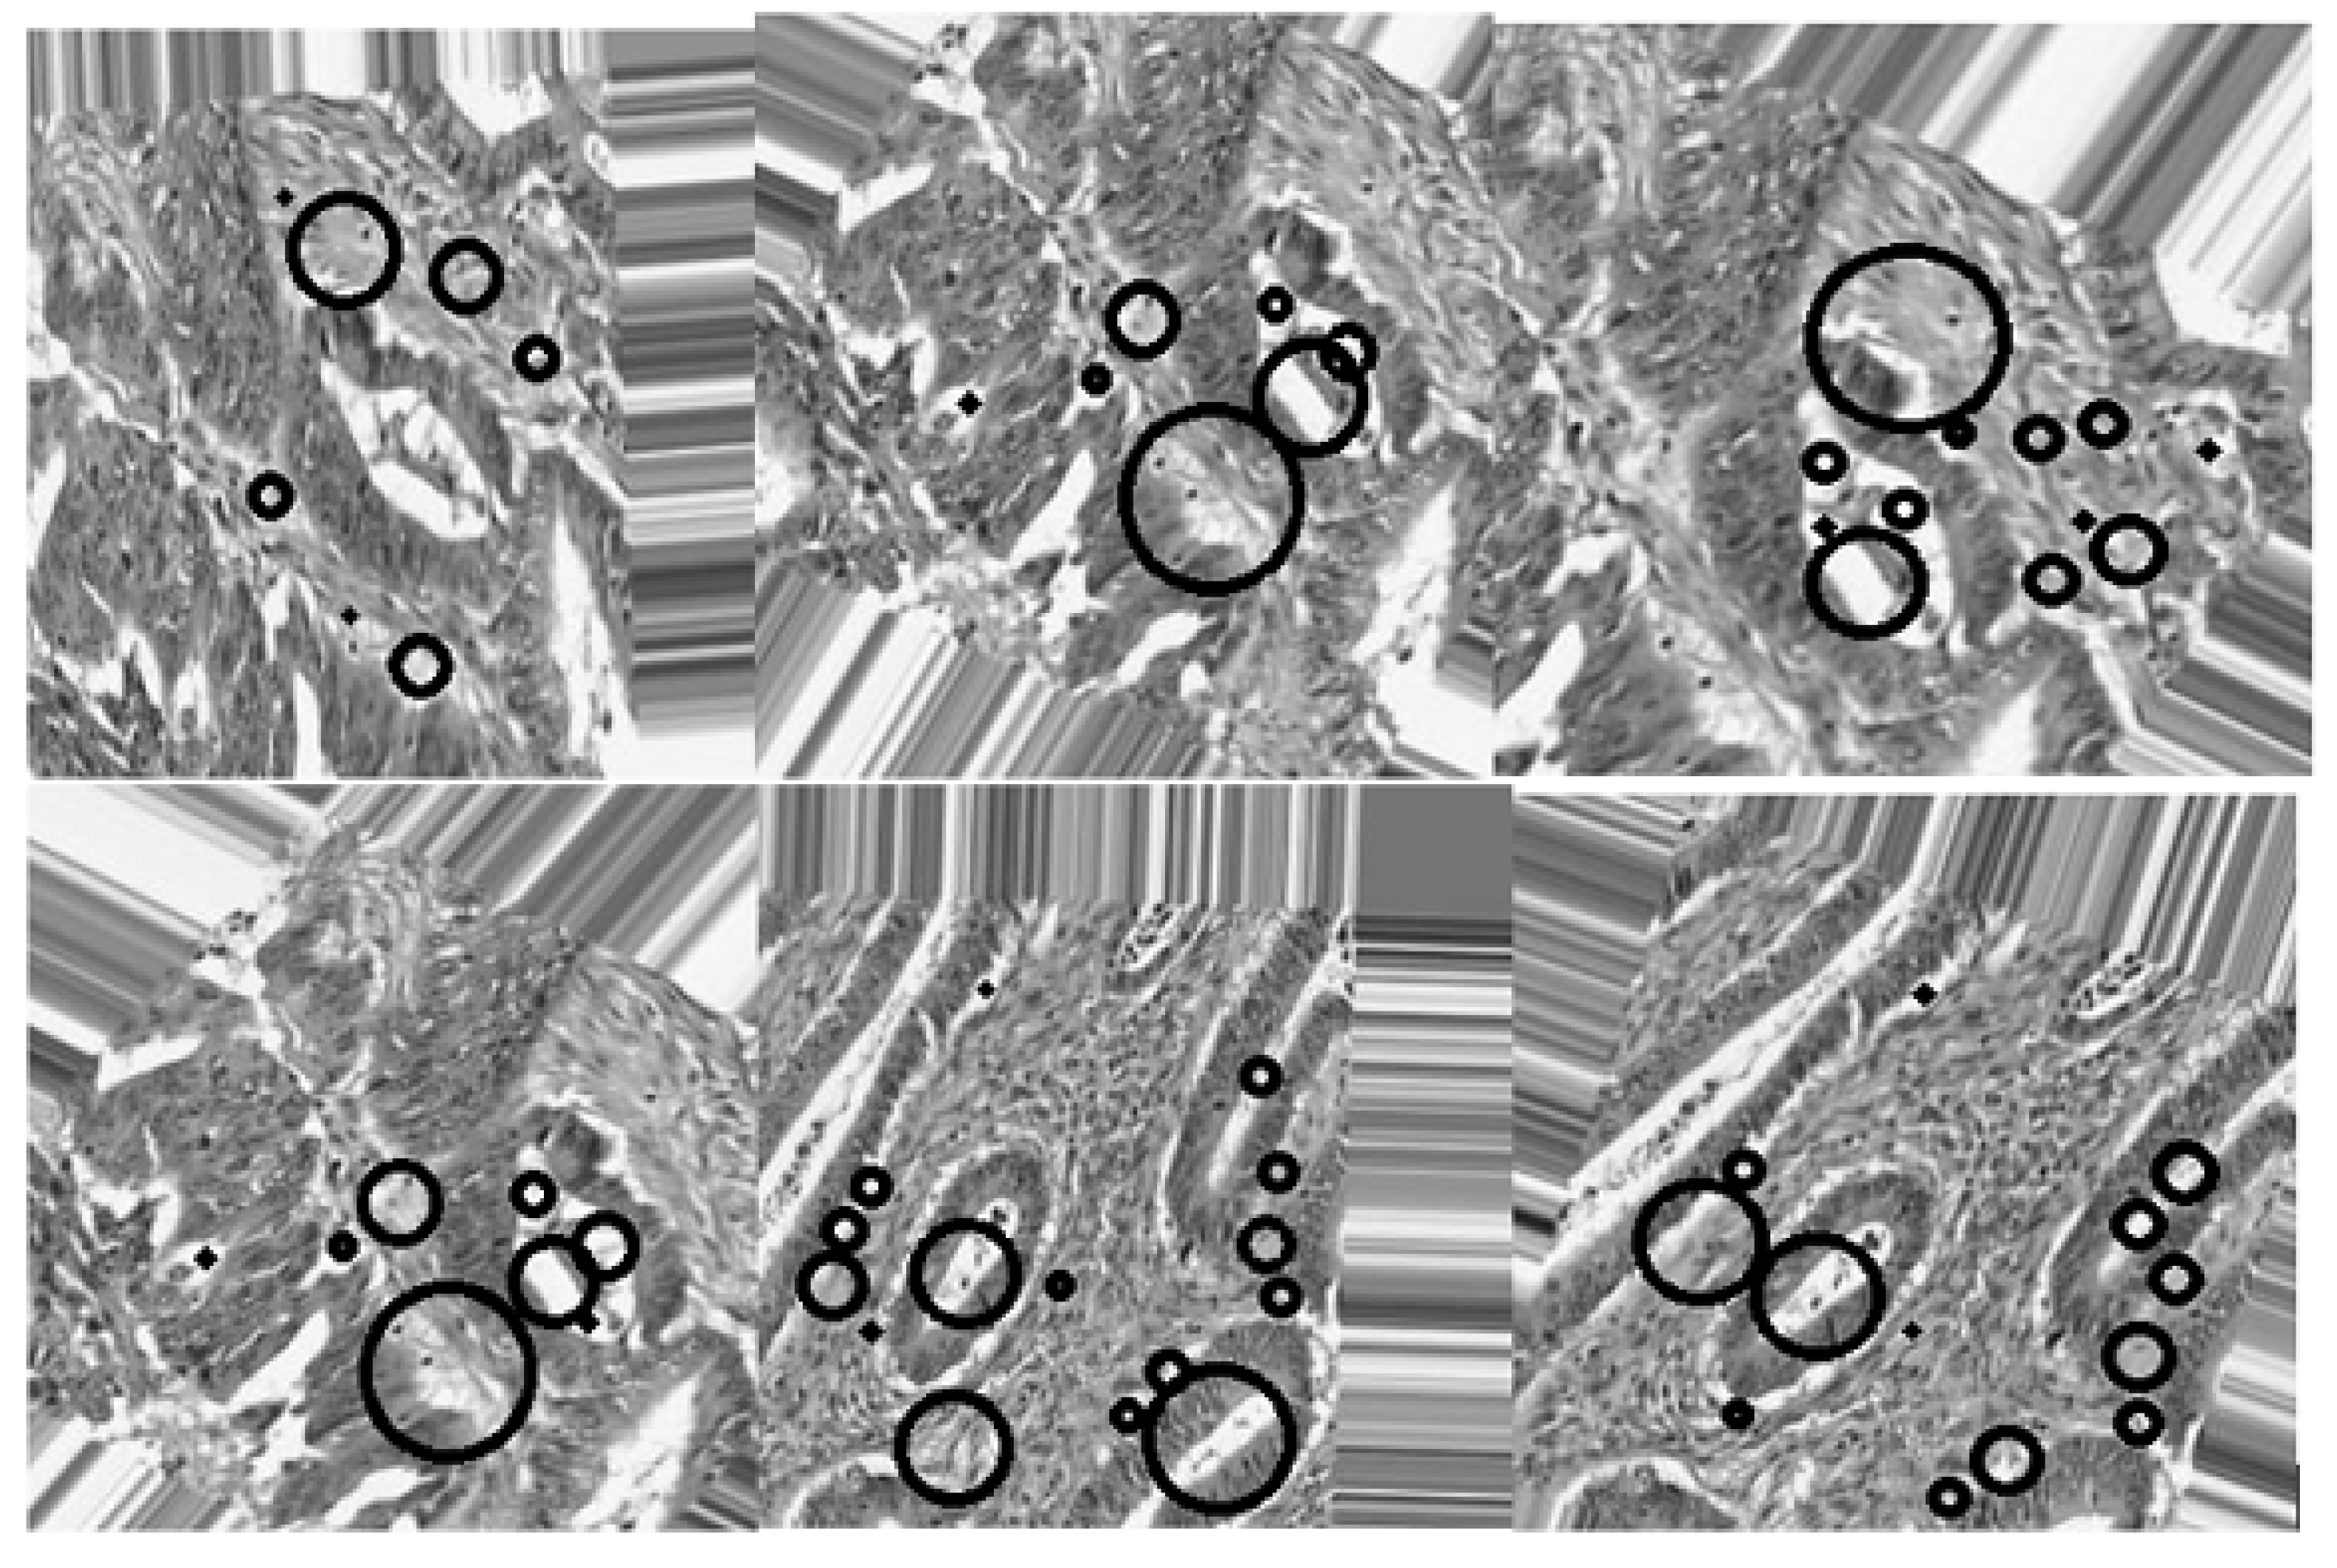

- The use of the connected component analysis method to group components with similar characteristics into binary masks that assist in separating overlapping and non-overlapping objects, thus avoiding over-segmentation.

- The binary masks from the connected component analysis method further aid in addressing the inaccurate segmentation of the image boundaries of intersecting objects, which is common with the active contours method. The proposed method clearly distinguishes the different ROIs from each other, clearly isolating and segmenting the cancerous lesions as visually documented in Section 3 and Section 4.